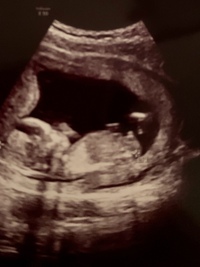

R先生というのは北海道の産婦人科医で 赤ちゃんが11〜13wくらいのときにエコーに映る ベビーナブというものの角度で 性別を判定できるという凄い方 普通、性別が分かるのはwくらいだったり 赤ちゃんが隠してしまってエコーで映らないと もっと 男の子 であれば 背骨に対しての 生殖器 の突起の角度が30℃以上 あり、 女の子 であればそれ以下、 背骨に対してほとんどが平行 にあるそう。 ベビーナブ 女の子 4dNgagolak 赤ちゃん 性別 エコー 11週 ベビーナブがわかる方お願いします どちらの性別でしょうか Yahoo 知恵袋

Babynub ベビーナブ 早期性別判定について調べていた時、babynubという言葉を知りました。 胎児の横向きからの突起の角度で性別を判断するというものです。 が、素人の私にはエコー写真を見てもさっぱり分かりませんでした。 確かに背骨に対して平行 baby nub(ベビーナブ)ってなに? アメリカをはじめとする海外では、 "The Nub Theory" といって、 11~12週頃の横向きのエコーに映る、突起の角度で男の子か女の子かを予想する。 いつから&見方は? お腹の赤ちゃん男の子か女の子かがわかる? 女の子のベビーナブは、身体の発達が進むとクリトリスになる部位です。 エコー写真に写った突起が背骨に対して並行で、足に向かって伸びていれば女の子という見立てになります